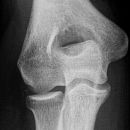

Radiusköpfchen; Greenspan

Beurteilungskriterien

Proximale Radiusfrakturen sind mit 50% die häufigsten Ellbogenverletzungen des Erwachsenen (Kinder 15%)! 50% der Radiusköpfchenfrakturen sind nicht disloziert und u.U. in den Standartprojektionen nicht nachweisbar -> bei klinischem Verdacht ist ein positives Fettpolsterzeichen in der seitlichen Aufnahme nahezu beweisend! Zusätzlich Greenspan-Aufnahme, evtl. CT oder MRT! Harmonische Darstellung des Radiusköpfchens? Impressionen? Stufe? Verdichtungen? Fissur? Knickbildung?